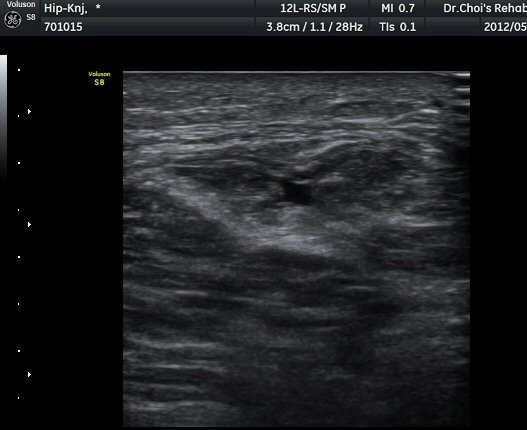

µÚÂÊ ´ëÅð ³»Ãø Ⱦ´Ü¸é°Ë»ç¿¡¼­ À̵ιڱ٠ÀåµÎ ¿ÜÃø¿¡¼­ ±ÙÀ°¼¶À¯¿Í ±Ù¸·¿¡ ÀÇÇØ Çü¼ºµÇ´Â

Á¤»óÀûÀÎ ±ÙÀ°ÀÇ ¸ð¾çÀÌ ¼Ò½ÇµÇ°í Àú¿¡ÄÚ º´º¯À¸·Î °üÂûµÈ´Ù(±×¸² 6). ŽÃËÀÚ¸¦ Á¶±Ý ¸»´ÜÀ¸·Î

À̵¿ÇÏ´Ï Àú¿¡ÄÚ º´º¯³»¿¡¼­ ±¹¼ÒÀûÀÎ ¼ö¾×Àú·ù°¡ °üÂûµÈ´Ù(±×¸² 7, 8).  À̵ιڱ٠ÀåµÎ Á¾´Ü¸é

°Ë»ç¿¡¼­ À̵ιڱ٠³»¿¡ ±¹¼ÒÀûÀÎ ±Ù¼¶À¯ ¼Ò½Ç°ú ¼ö¾×Àú·ù°¡ °üÂûµÈ´Ù(»çÁø 9, 10).